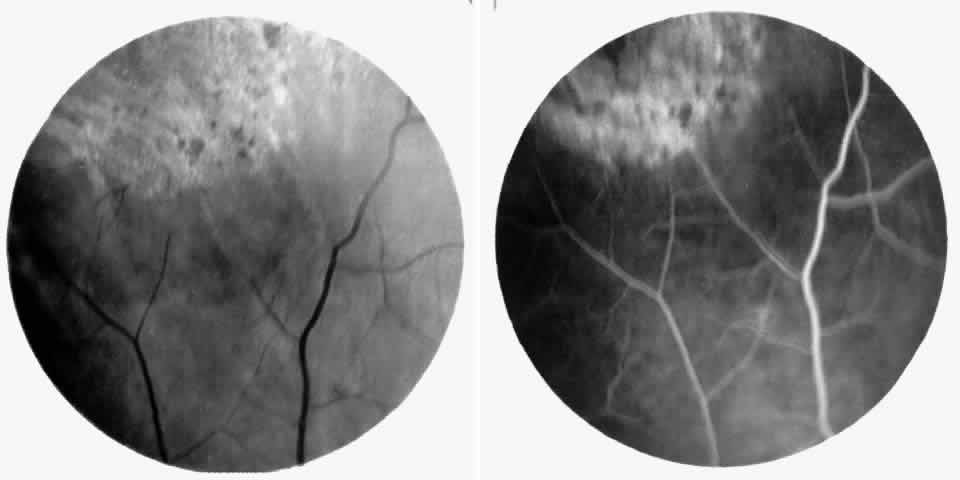

STAGE II: PERIPHERAL ARTERIOLAR-VENULAR ANASTOMOSES. Following occlusion of the terminal arterioles, anastomotic channels form to channel the blood from the occluded arteriole to the nearest venules. These anastomoses form at the interface between the perfused and nonperfused retina. Most likely, they are dilated preexisting capillaries rather than new vessels, since they do not leak on fluorescein angiography. The redirection of blood flow is probably due to hydrostatic forces (Figs. 22 and 23).

Fig. 22. A. Photograph of the peripheral retina, demonstrating capillary occlusions and exudate at the margin of perfused retina. B. Fluorescein angiogram of irregular capillary border, with capillary stumps extending into nonperfused retina and an arteriolar-venular anastomosis demonstrating stage II retinopathy.

Fig. 23. Fluorescein angiogram of continuous arteriolar-venular anastomosis demonstrating stage II retinopathy. (Note that this is the same eye demonstrating the qualitatively abnormal peripheral capillary border in Figure 25.)